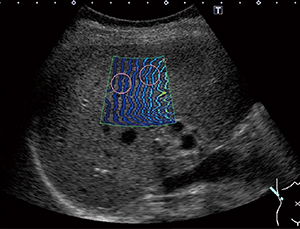

●Shear wave with Smart maps

プローブを静止した状態で,組織を圧迫することなく組織の硬さの絶対値を求めることができます。プローブからのPush Pulseによってせん断波を発生させ,その伝搬速度をカラーマッピング表示することにより,硬さの空間的分布を表示できます(図1)。これに加え,せん断波の到達時間を等高線表示する東芝独自の表示モードにより,せん断波の伝播状態を確認して検査結果の信頼性を判断することができます(図2)。

図1 カラーマッピング表示 |

| (図1,2画像ご提供:兵庫医科大学・飯島尋子先生) | |